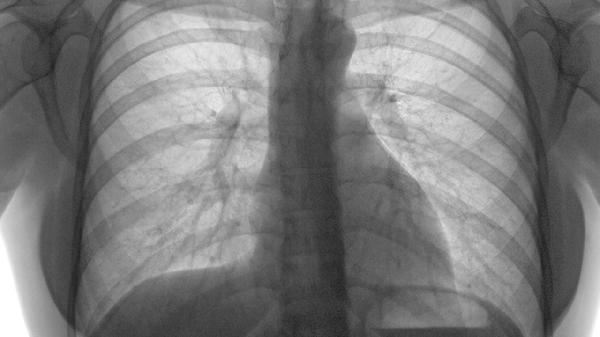

低剂量螺旋CT是目前最有效的早期筛查手段,建议高危人群每年检查一次。普通X光片很难发现小于1cm的病灶,等它能照出来时往往已是中晚期。